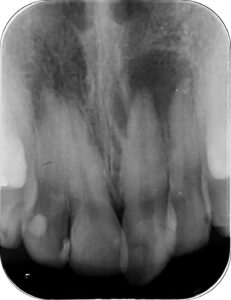

当院に上顎前歯の付け根あたりの歯肉に無痛性の膨らみを感じた患者様が来院されました。

他院での虫歯治療による詰め物がなされていたため、歯髄壊死による歯根嚢胞を疑いエックス線CTを撮影しました。

CT画像では顎骨は歯根を取り囲むように大きく吸収されており、嚢胞の完治は容易ではないことが推察されました。